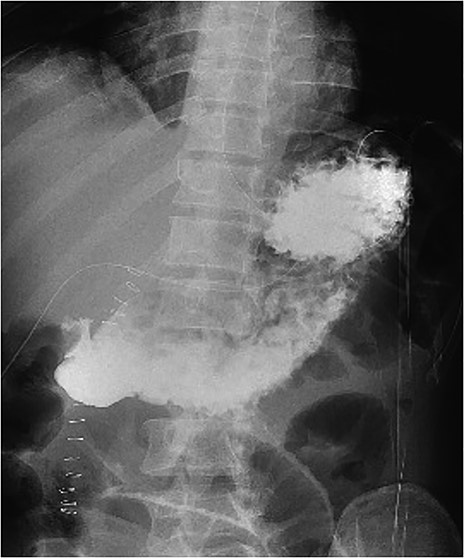

On examination in the emergency department, he was found to have localized peritonism to the epigastrium and was diaphoretic. An urgent erect chest radiograph (Figs 1 and 2) was revealing of gross pneumoperitoneum, presumably of a hollow viscous perforation as the source. General surgery was consulted after the presence of free air was detected. In the setting of the patient’s virgin abdomen and unremarkable surgical history, with peritonism and free intraperitoneal gas, the patient proceeded directly to urgent exploratory laparotomy with concurrent resuscitation measures, including intravenous fluid resuscitation and placement of an indwelling catheter.

The patient was transferred to the surgical ward for ongoing cares, remaining nil by mouth and commenced on intravenous antibiotics and proton pump inhibitor infusion. On post-operative day 3, a follow-through contrast study showed no leak of enteric contents from the stomach (Fig. 3) with transit of the contrast into the duodenum, and a concurrent ileus was shown with prominent small bowel loops (Fig. 4). A clear fluid diet was initiated, with gradual upgrade before discharge to usual residence and follow-up gastroscopy as outpatient.